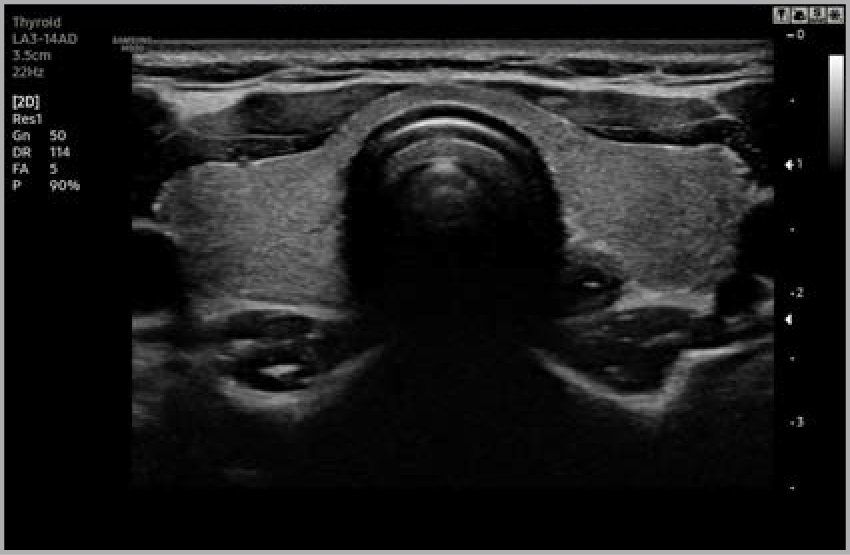

Le ecografie sono, invece, molto utilizzate per lo studio del collo (tiroide, linfonodi), dell’addome (fegato, reni, milza, pancreas, eccetera), della pelvi (vescica, utero, ovaie, prostata), delle vene e delle arterie (carotidi, aorta, eccetera), dell’apparato muscolare (muscoli, tendini, legamenti).

- Ecografia Generale (es. muscolare, articolare, addominale, renale, epatica, vie urinarie, testicolare, prostatica, tiroidea, linfonodi, ecc.)

• Ecografia Tiroidea